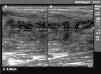

Primer episodio de piomiositisEl 15 de noviembre de 2006 inició un cuadro de molestias en la región deltoidea derecha, sin antecedente traumático, con dolor a la palpación, enrojecimiento y calor local. Se encontraba afebril y no presentaba malestar general. Se realizó ecografía, en la que se observa colección anecoica extensa de 5 × 10cm en el músculo deltoides derecho compatible con absceso muscular (fig. 1).

Se decidió realizar cultivo tras la punción-aspiración y se determinó la presencia de S. aureus. Tras 8 días de tratamiento con ciprofloxacino la mejoría clínica era prácticamente total, si bien ecográficamente no mostraba una recuperación completa. A la semana se le permitió iniciar entrenamientos individuales progresivos, y a los 10 días fue dado de alta para entrenarse con el resto de los jugadores del equipo.